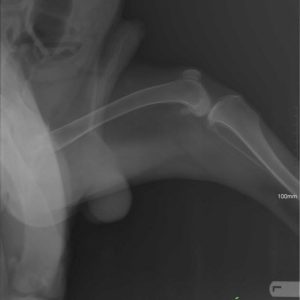

Köszönjük szépen Alexander Englert-nek, hogy Mex diszplázia műtéti költségét finanszírozta! Még 2 és fél hónap rehabilitáció és kereshetünk neki új gazdit! Category: HírekBy Csillag Alexandra2017-09-14 Share this post Share on FacebookShare on Facebook Share on XShare on X Author: Csillag Alexandra http://www.ebarvahaz.hu Post navigationPreviousPrevious post:SnowNextNext post:Közeleg a tél!Related postsPályázati eredmény2026-03-17Tami és a babák2026-01-22Cuki újoncaink2025-10-27IV. TÖKéletes nap az EbÁrvaházban2025-10-17Kutyás családi és nyílt nap a Kraft SE szervezésében2025-09-01Karamell kisgengszter berobbant a menhely életébe <32025-08-05